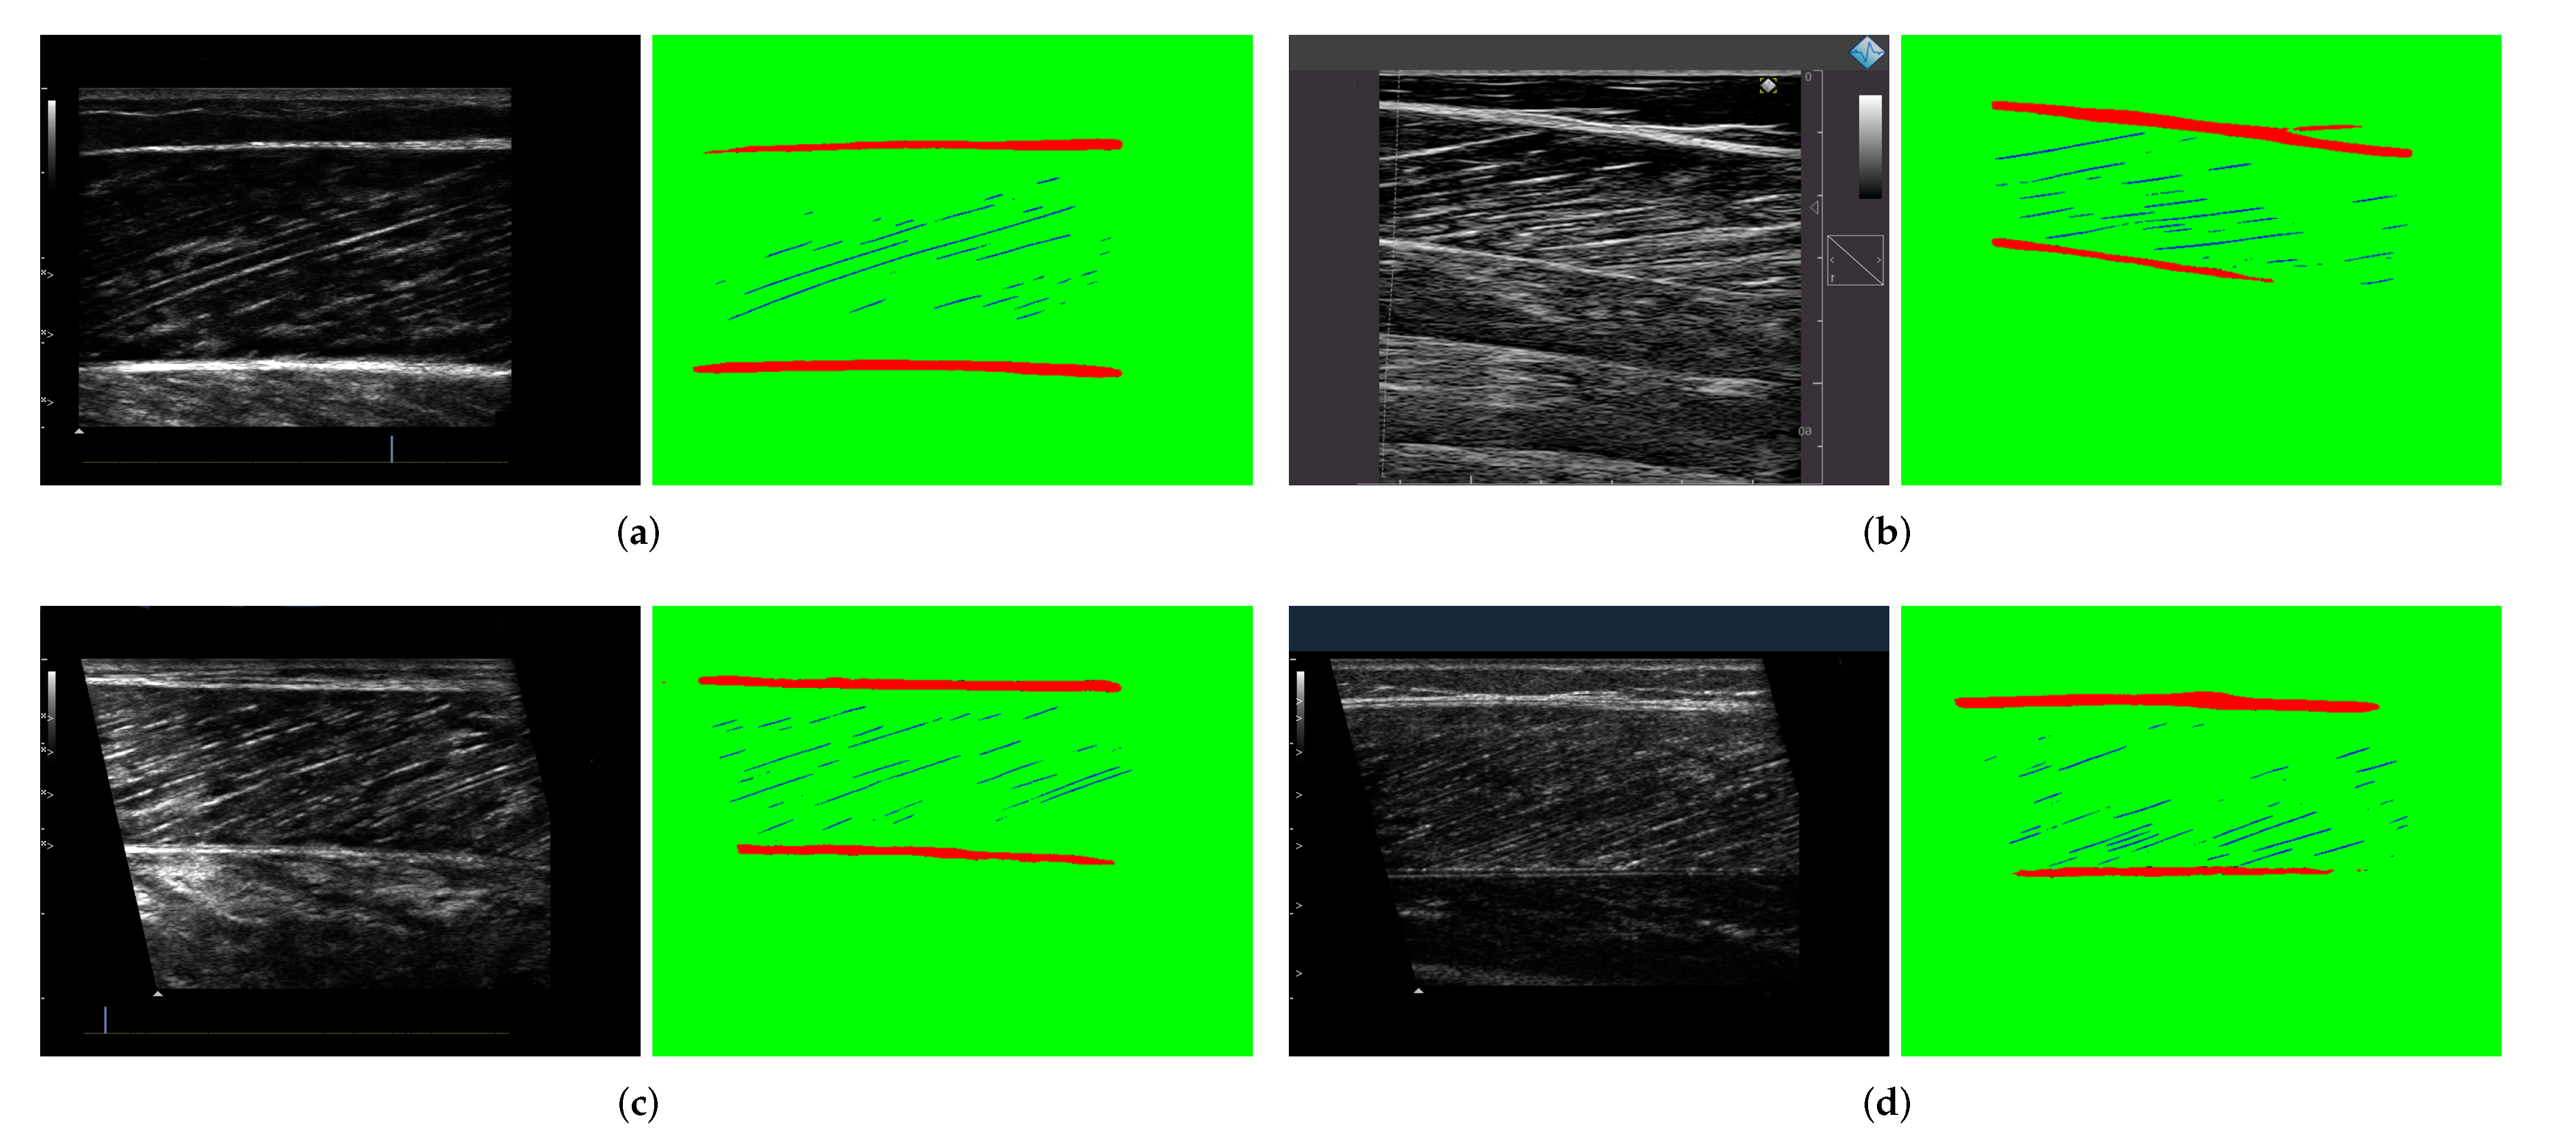

We collected ultrasound image datasets from different types of movements conducted by different groups of the population (including young people, elderly people, etc.). These data include a large number of videos and images, which are obtained from muscle tissues in different parts of the body (medial and lateral gastrocnemius, vastus lateralis, tibialis anterior) using a variety of ultrasound devices.To ensure the diversity of data, we collected data from different sources. Some of these were collected by experts from Shenzhen Institute of advanced research, Chinese Academy of Sciences, and some are from the research of J. Cronin et al. [26]. A set of 508 samples was obtained by cutting images and randomly extracting videos by frame. Three researchers used FIJI software [32] to manually label the dataset to generate masks. Each mask is divided into three parts with different colors, with the blue part representing muscle fibers, the red representing aponeuroses, and the green representing background. Figure 4 shows the samples of the manually labeled dataset. The dataset is divided into a training set and a validation set according to the ratio of 9:1. Another 50 samples are randomly selected from the videos besides the training set to form a test dataset, which ensures the reliability of experiment results. These data have received ethical approval from the relevant committees of Shenzhen Institutes of Advanced Technology, CAS.

Figure 4.

Samples from the training dataset. (a) Some original ultrasound images collected from multiple subjects. (b) The ground truth marked by the experimenters using Fiji software.